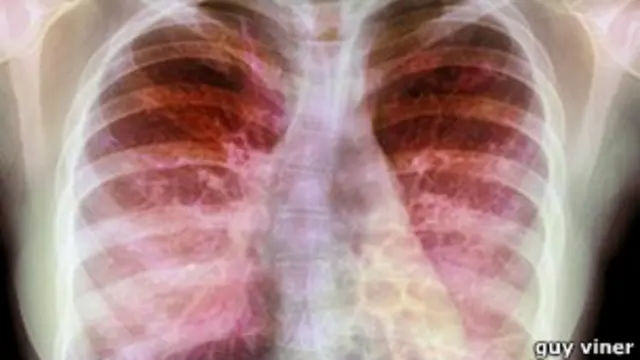

وتؤثر هذه العدوي الناتجة عن البكتريا المتفطرة الخراجية على الأعضاء الداخلية للجسم، وخاصة الرئة والجهاز الهضمي، حيث يؤدي إلى صعوبة في التنفس، كما يجعل من الصعب أيضا هضم الطعام بشكل طبيعي.

ويؤدي هذا المرض إلى تلف في الرئة، وعلاج الأشخاص الذين يصابون به قد يكون صعبا للغاية، ويتطلب الخضوع لشهور من العلاج بالعقاقير السمية.